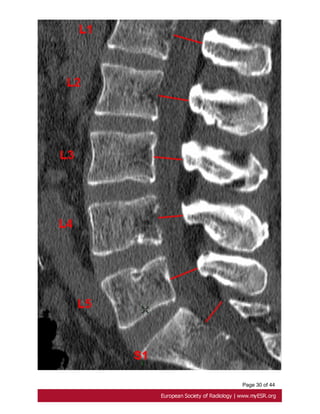

the midsagittal vertebral body diameter [28]. Fig. 19 on page 29, Fig. 20 on page 31

Fig. 19: Oosterhof criteria of dural ectasia. A dural sac ratio is calculated for each level

by dividing the sagittal dural sac (red arrows)diameter by the midsagittal vertebral body

diameter on CT scan.

Fig. 20: Oosterhof criteria of dural ectasia. Midsagittal vertebral body diameter (red

arrows) on CT scan.

Page 31 of44 Fig. 19: Oosterhof criteria of dural ectasia. A dural sac ratio is calculated for each level by dividing the sagittal dural sac (red arrows)diameter by the midsagittal vertebral body diameter on CT scan.

Page 33 of44 Fig. 20: Oosterhof criteria of dural ectasia. Midsagittal vertebral body diameter (red arrows) on CT scan.